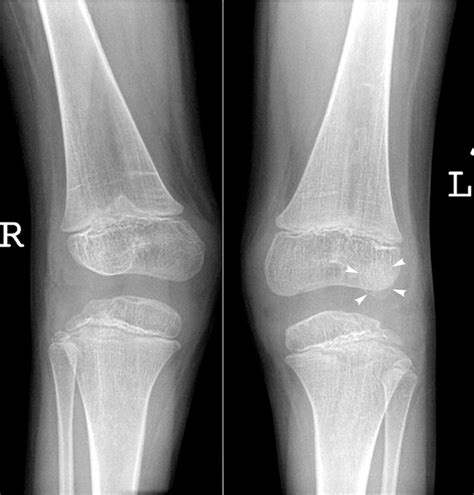

• Imaging Tests: X-rays, MRI, or CT scans may be ordered to assess the extent of the injury and check for any associated fractures or ligament damage.